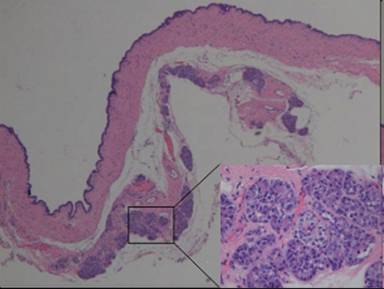

Grossly, the specimen measuring 7x6x3 cm in size was a multiloculated cystic lesion with a thin wall and contained watery clear fluid. No papillary or solid components were seen (Figure 3). Microscopically, the cyst was lined by a single layer of cuboidal cells without stratification or papillary growth (Figure 4).

Figure 4. The epithelium was composed by a single layer of cuboidal cells. |

The lining cells had eosinophilic to basophilic cytoplasm without nuclear atypia, mitosis, or mucinous differentiation. No ovarian-like stroma was seen. Occasional small clusters of residual pancreatic elements including islet cells and acinar glands were also seen in the cystic wall (Figure 5).